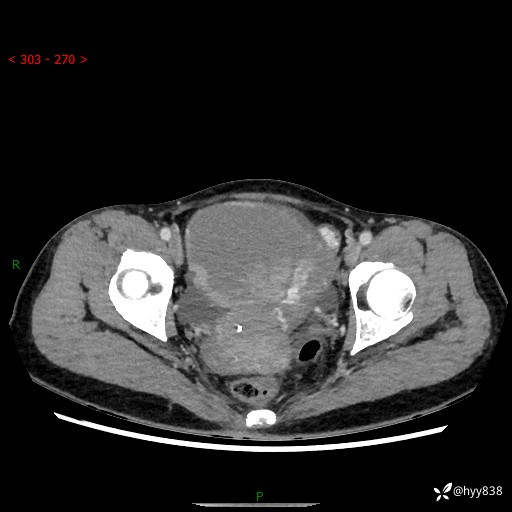

【患者信息】:女,50岁

【主诉】:外院超声发现腹盆肿块,为进一步诊治来我院,门诊已“盆腔肿块”收入院。

腹盆CT平扫+增强

【临床诊断】:盆腔肿瘤